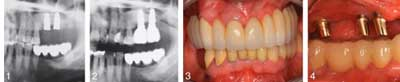

Two surgeries are frequently required for tooth replacement with dental implants; however, clinicians must allow for adequate healing time between the procedures. Most patients want to minimize the overall recovery time and thus desire the surgeries be done close together. A study in the Journal of Oral Implantology looks specifically at healing times between the two dental procedures involving tooth replacement.ADDITIONAL READING |Improved dental implant surface and hygiene boost restoration success With tooth loss, the jawbone can shrink, making it impossible to replace the missing teeth with dental implants without risk of nerve or sinus damage. An additional surgery may be required to assure that adequate jawbone height and width are available for implant placement.

The study looks at 14 patients who underwent two procedures involving tooth replacement. In the first procedure, patients received a bone substitute, composed from nanocrystalline hydroxyapatite, which was grafted into the patient’s jaw. This synthetic material provided scaffolding for new bone growth, expanding into patients’ upper jawbone. Half of the patients then waited three months while the other half waited six months before undergoing the second procedure, placement of the dental implant(s).ADDITIONAL READING |New material used in molar extraction sites optimizes bone regeneration and dental implant stability The study found similar results among patients three years after the dental implants, whether patients waited three or six months between procedures. The 14 patients collectively received 24 implants in the upper jaw, and only one patient lost an implant. No implants were loose, and only a few showed signs of plaque or changes to soft tissue. The authors conclude that synthetic bone seems to need only three months to become secure enough for dental implants to be placed successfully in the jaw. The additional three months between surgical procedures had no significant long-term effect among the studied patients. Full text of the article “Nanocrystalline hydroxyapatite-based material contributes to implant stability after three months: A clinical and radiological 3-year follow-up investigation,” Journal of Oral Implantology, Vol. 40, No. 1, 2014, is now available online.About Journal of Oral Implantology The Journal of Oral Implantology is the official publication of the American Academy of Implant Dentistry. It is dedicated to providing valuable information to general dentists, oral surgeons, prosthodontists, periodontists, scientists, clinicians, laboratory owners and technicians, manufacturers, and educators. The JOI distinguishes itself as the first and oldest journal in the world devoted exclusively to implant dentistry. For more information about the journal or society, please visit: www.joionline.org.